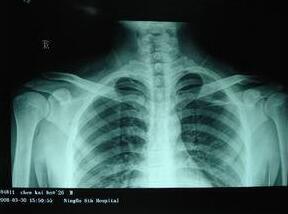

(图:胡女士右肩治疗前照片)

(图:胡女士复查时拍摄照片)